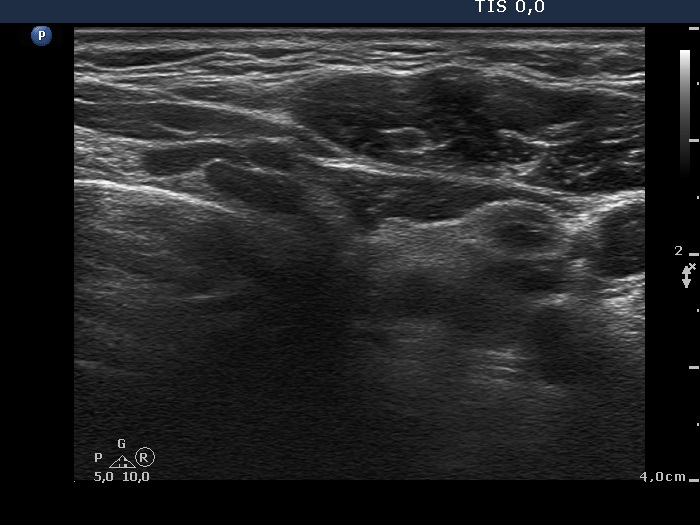

Study on 100 consecutive patients with thyroid nodule - case 032 (ultrasonographic picture 5)

Left lobe, transverse scan. Here the depth is set to 4 cm. This lobe is normal in size and contains discrete hypoechogenic areas.